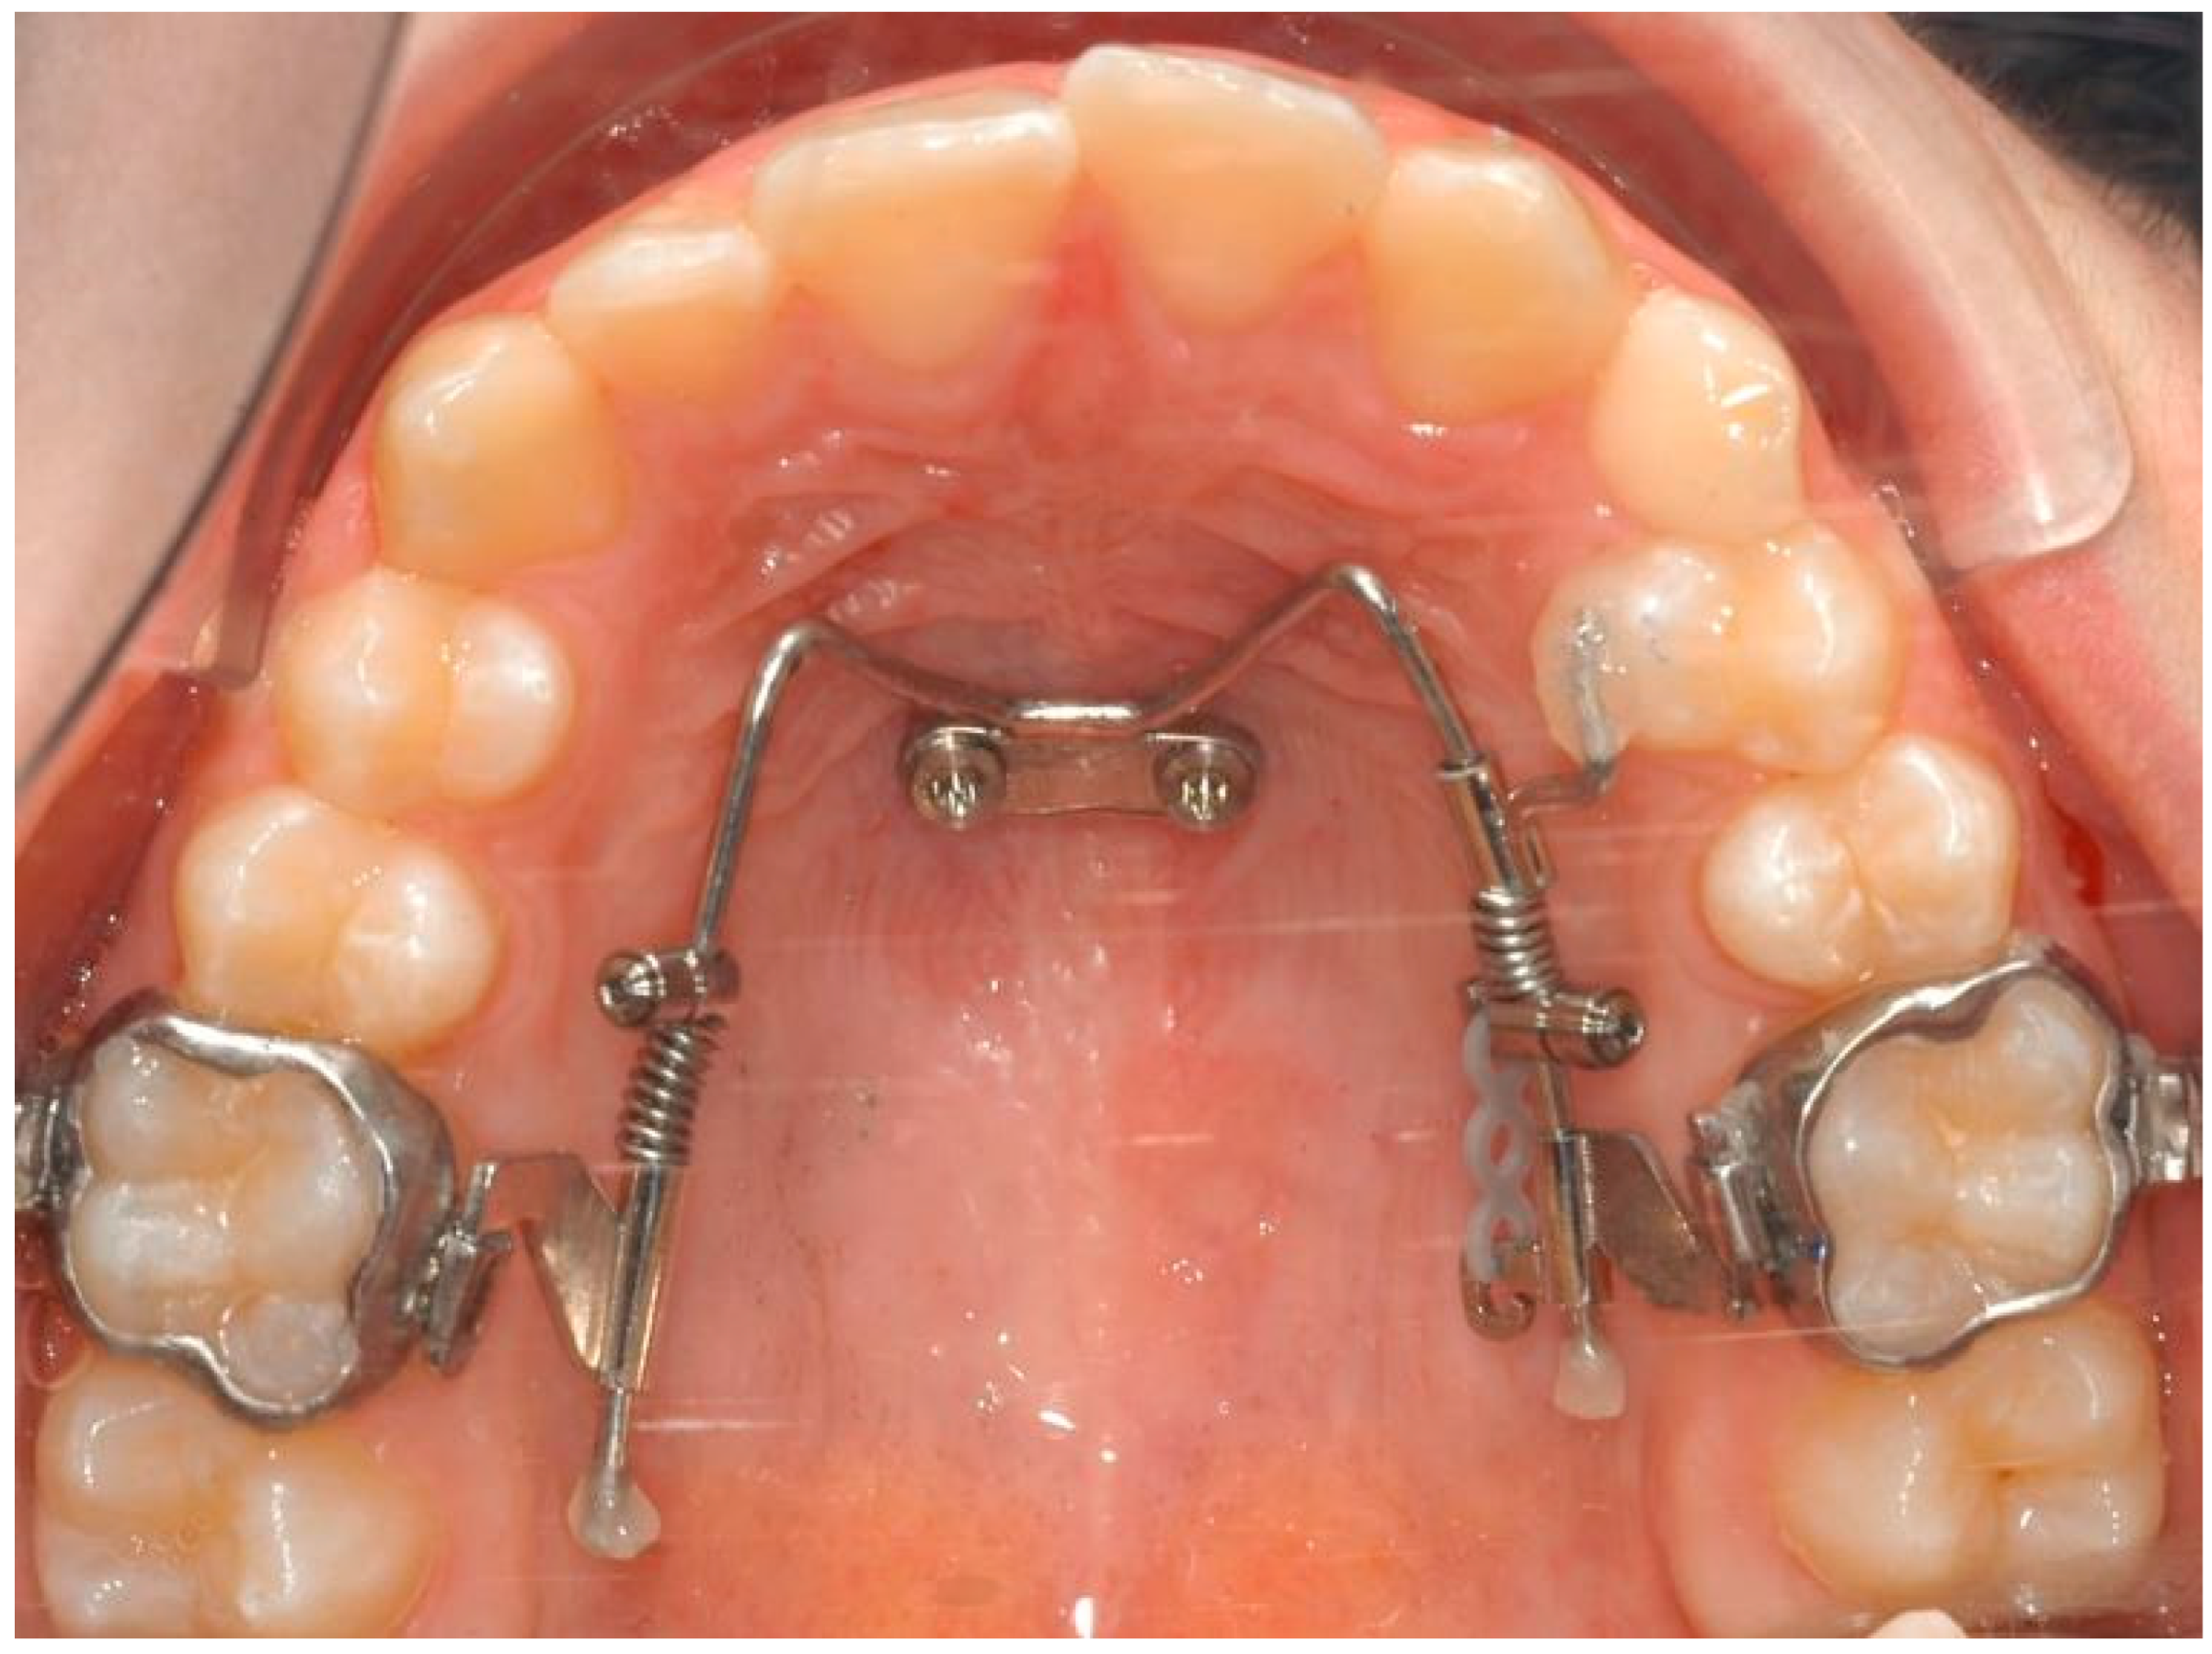

2.1. The Appliance

- Wilmes, B.; Nanda, R.; Nienkemper, M.; Ludwig, B.; Drescher, D. Correction of upper-arch asymmetries using the Mesial-Distalslider. J. Clin. Orthod. 2013, 47, 648–655. [Google Scholar] [PubMed]